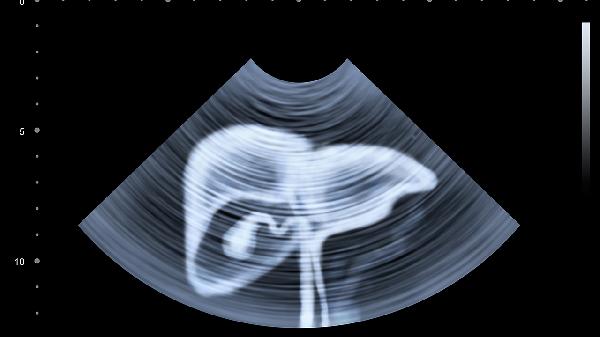

腸易激綜合征、慢性胃炎等疾病常伴腹脹腹痛。膽囊炎發(fā)作時(shí)右上腹疼痛向右肩放射。若持續(xù)絞痛伴嘔吐、便血需立即就醫(yī),通過(guò)胃腸鏡、腹部B超排除腸梗阻或腫瘤等重癥。